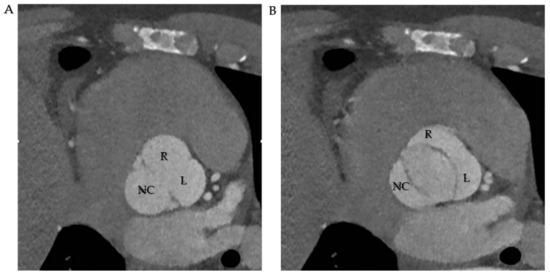

7.2. Cardiac Computed Tomography

Cardiac computed tomography (CCT) complements US scans in BAV diagnosis. It is relevant in determining aortic dilation, the anatomical edges and correlation with closer structures, and discovering other pathologies correlated with BAV, such as aortic coarctation. Therefore, the radiological protocol is scheduled to determine those features useful for surgeons in the act of choosing traditional surgical approach or transcatheter aortic valve replacement (TAVR) [94] (Figure 8).

Figure 8.

(A,B). CT scan in R-L cusp fusion. (A) Three sinuses are represented. (B). Opening mechanism in fusion pattern. Abbreviations; R, right coronary cusp; L, left coronary cusp; NC, non-coronary cusp.